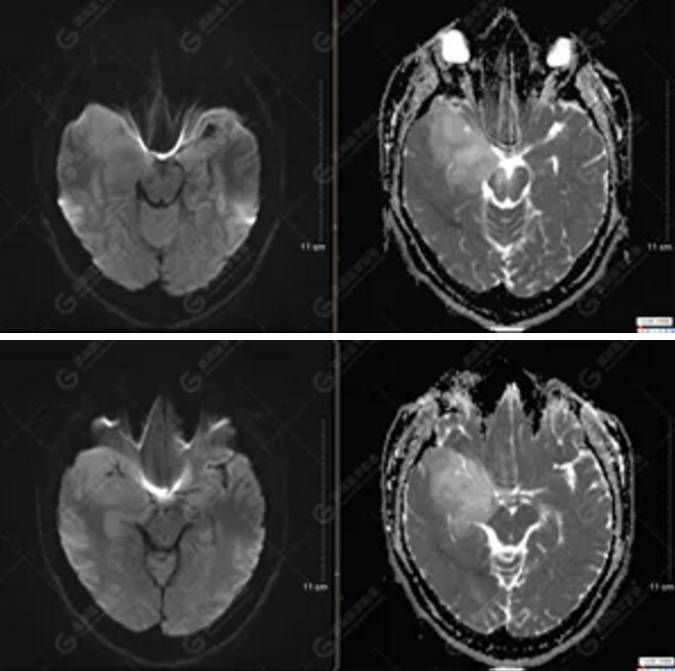

以上為DTI成像,圖1為皮質(zhì)脊髓束,圖2為胼胝體束,圖3為扣帶回束,圖4為額枕束。DTI成像示右側(cè)額枕束前部明顯受壓、部分未見顯示;胼胝體束、雙側(cè)扣帶束、皮質(zhì)脊髓束及左側(cè)額枕束形態(tài)可,纖維束未見明顯破壞,未見明顯稀疏減少。